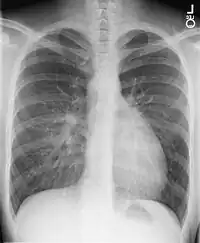

•Chest X-Ray: On chest X-ray (CXR), transposition of the great vessels typically shows a cardio-mediastinal silhouette appearing as an "egg on a string ", in which the enlarged heart represents an egg on its side and the narrowed, atrophic thymus of the superior mediastinum represents the string.[4]